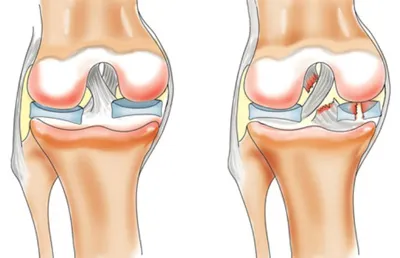

Артроскопія

Артроскопія — це високотехнологічний метод діагностики та лікування суглобів через кілька невеликих проколів. На відміну від класичної відкритої операції, артроскопія не потребує великого розрізу, що дозволяє зменшити травматизацію тканин, прискорити реабілітацію та знизити ризик ускладнень.